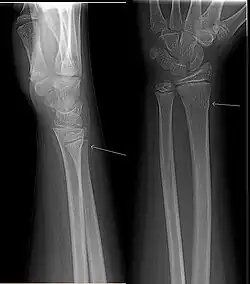

Een zoethoutbreuk of vouwfractuur is een bijzonder soort fractuur. In de praktijk spreekt men gewoonlijk van een twijgbreuk of greenstickfractuur: Het bot breekt als een twijg waarbij de schors intact blijft. Een greenstickfractuur kan voorkomen wanneer het bot nog niet gehard is. Het buigt als het ware, maar breekt niet. Er blijft één cortex intact, terwijl de andere breekt. Greenstickfracturen ontstaan gemakkelijk bij jonge kinderen en dieren. Op een röntgenfoto is er bijna niks van te zien, alleen een klein bultje. Bij repositie is het noodzakelijk om de andere, niet gebroken, cortex alsnog te breken om te voorkomen dat het bot terugveert en de oude angulatiestand aanneemt.